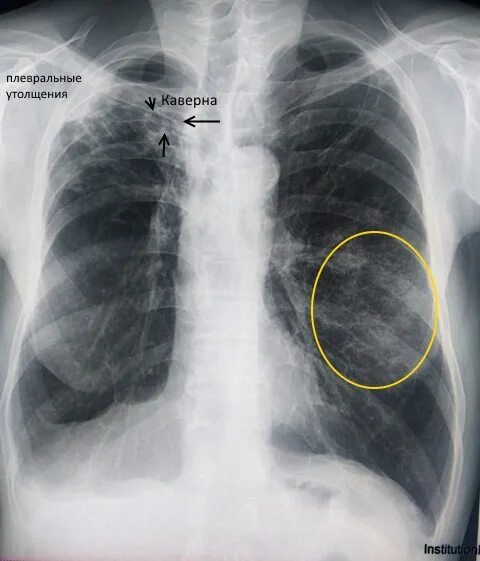

Метатуберкулезные изменения в легких что это означает